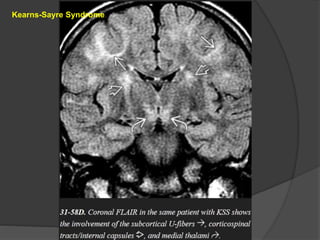

Kearns-Sayre Syndrome KSS typicallypresents in older children or young adults and is characterized by short stature, progressive external ophthalmoplegia, retinitis pigmentosa, sensorineural hearing loss, and ataxia. Imaging CT scans show variable symmetric basal ganglia calcifications. Mild cortical and cerebellar volume loss is common. MR shows increased signal intensity in the basal ganglia, WM, and cerebellum on T2/FLAIR. The subcortical arcuate fibers, corticospinal tracts, cerebellum, and posterior brainstem are involved early in the disease course while the periventricular WM remains relatively spared. DWI shows reduced diffusivity in the brainstem and subcortical WM. MRS demonstrates elevated lactate.